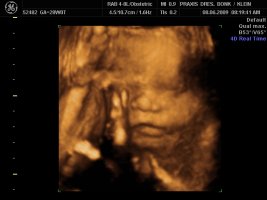

Und dann haben wir endlich unser Video gemacht, Zeit hatten wir ja nun genug und das ist voll süß geworden, sie war wohl auch wie Mama müde, denn sie hatte öfter mal gegähnt und mit den Augen geblinzelt :love1 ...kann es kaum noch erwarten die Kleine in die Arme zu nehmen :applaus

Und wir haben endlich ein Beweisfoto bekommen, dass es ein Mädchen ist...

Hier ein paar Bilder von Montag, neben dem Video haben wir auch sehr viele Bilder mitbekommen.... :love1

Anhänge

• Bild 1.jpg

Bild 1.jpg

72,4 KB · Aufrufe: 72

• Bild2.jpg

Bild2.jpg

75,1 KB · Aufrufe: 72

• Bild3.jpg

Bild3.jpg

61,5 KB · Aufrufe: 72

@Imke ui was für schöne Bilder, will auch! *jammer*